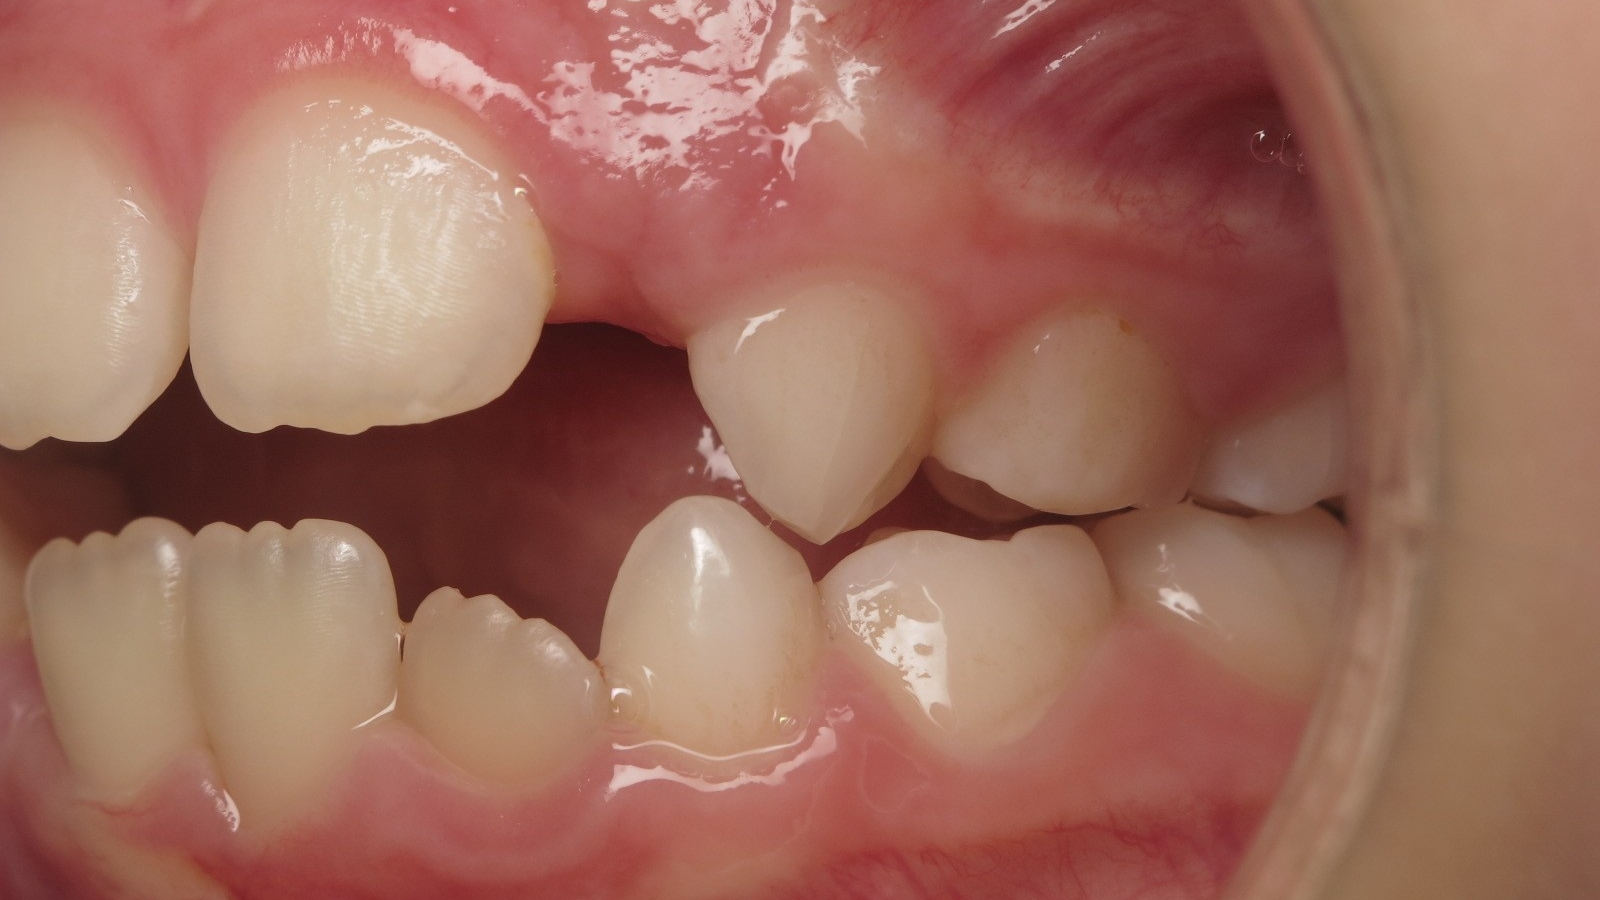

sectionnel multibagues pendant 8 mois

surveillance évolution de la dentition en cours

bilan début et en cours de traitement